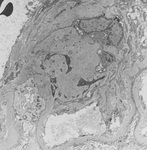

Diabetic kidney disease

Diabetic kidney disease: mesangial expansion due to increased mesangial matrix and decreased degradation of glycosylated collagen

From the collection of Dr Raoul Fresco; used with permission